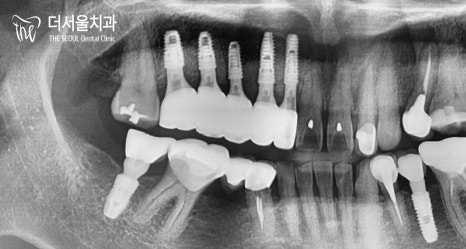

이분은 # 12 – # 15가

브릿지로 연결되어 있었는데요.

짐작하건대 매복치아 때문에

이렇게 길~~~~~~~게

연결을 해둔 것 같습니다.

그래서 그런지 수명이 짧을 수밖에요.